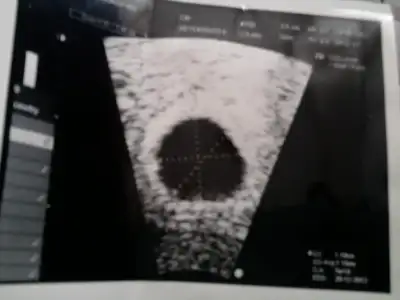

günaydın kızlar canım çok sıkkın benmbugün başka bi doktora gittim canım çok sıkıldı kahrolası şehirde doğru düzgün doktor yok ki bugün daha önceki gebeliğimi farketmeyipte onun yüzünden kürtaja girdiğim doktora gittim canımıda sıktı yok düzgün değil falan diye gider bu bebek falan diye oysaki dün kendi drum kalp atışı için gün vermişti şimdi çok korkuyorum ben

canım bende kötüyüm ya bu doktorlar niye böyle canımı sıktı benimde 10 gün önceki değerin düşükmüş dış gebelik olabilir bilmem ne ağladım ağladım şimdi kan sonucunu bekliyorum ama umudum kırıldı yaa nolcak halimiz devlet hastanelerinden nefret ediyorummmmmmm